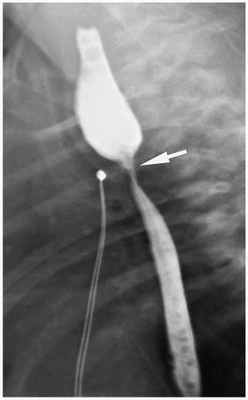

Также проводится рентген-контрастное исследование. Через зонд в верхний сегмент пищевода вводится не более 1 мл контраста. При наличии верхнего трахеопищеводного свища, кроме пищевода окрашивается ещё и трахеобронхиальное дерево.

Лучевое исследование включает выполнение рентгеноскопии и рентгенографии легких, эзофагографии,

МСКТ грудной клетки. Контрастное исследование пищевода проводят очень осторожно, используя водорастворимые или масляные вещества, которые вводятся через зонд (применение сульфата бария в этих случаях недопустимо). Трахеопищеводный свищ требует проведения тщательной дифференциальной диагностики с изолированной атрезией и стенозом пищевода, ахалазией кардии, дисфагией различного генеза.